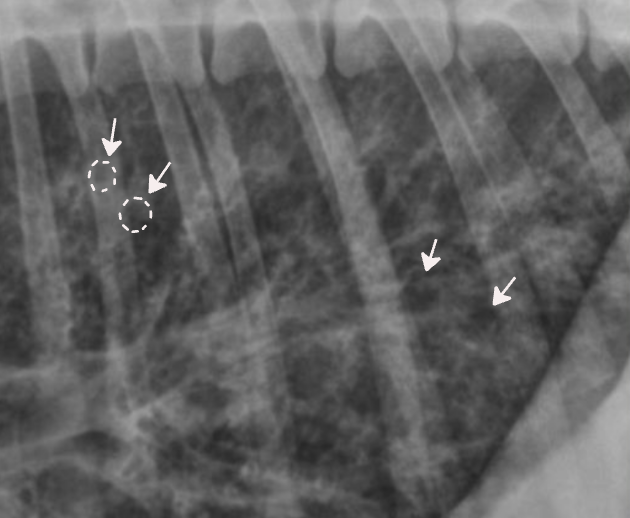

| โณ๏ธ Interstitial pattern |

๋ฒฝ์ด ๋๊บผ์์ง๊ณ ๊ณต๊ธฐ๊ฐ ์ฐจ๋ฉด์ ์ง์ ๋ถํ๊ฒ ๋ํ๋๋ ๋ชจ์.![]() |

| + Nodular (๊ตฌ์กฐ์ฑ ๊ฐ์ง ํจํด) : ํ๊ฒฐ์ |

![]() ![]() |